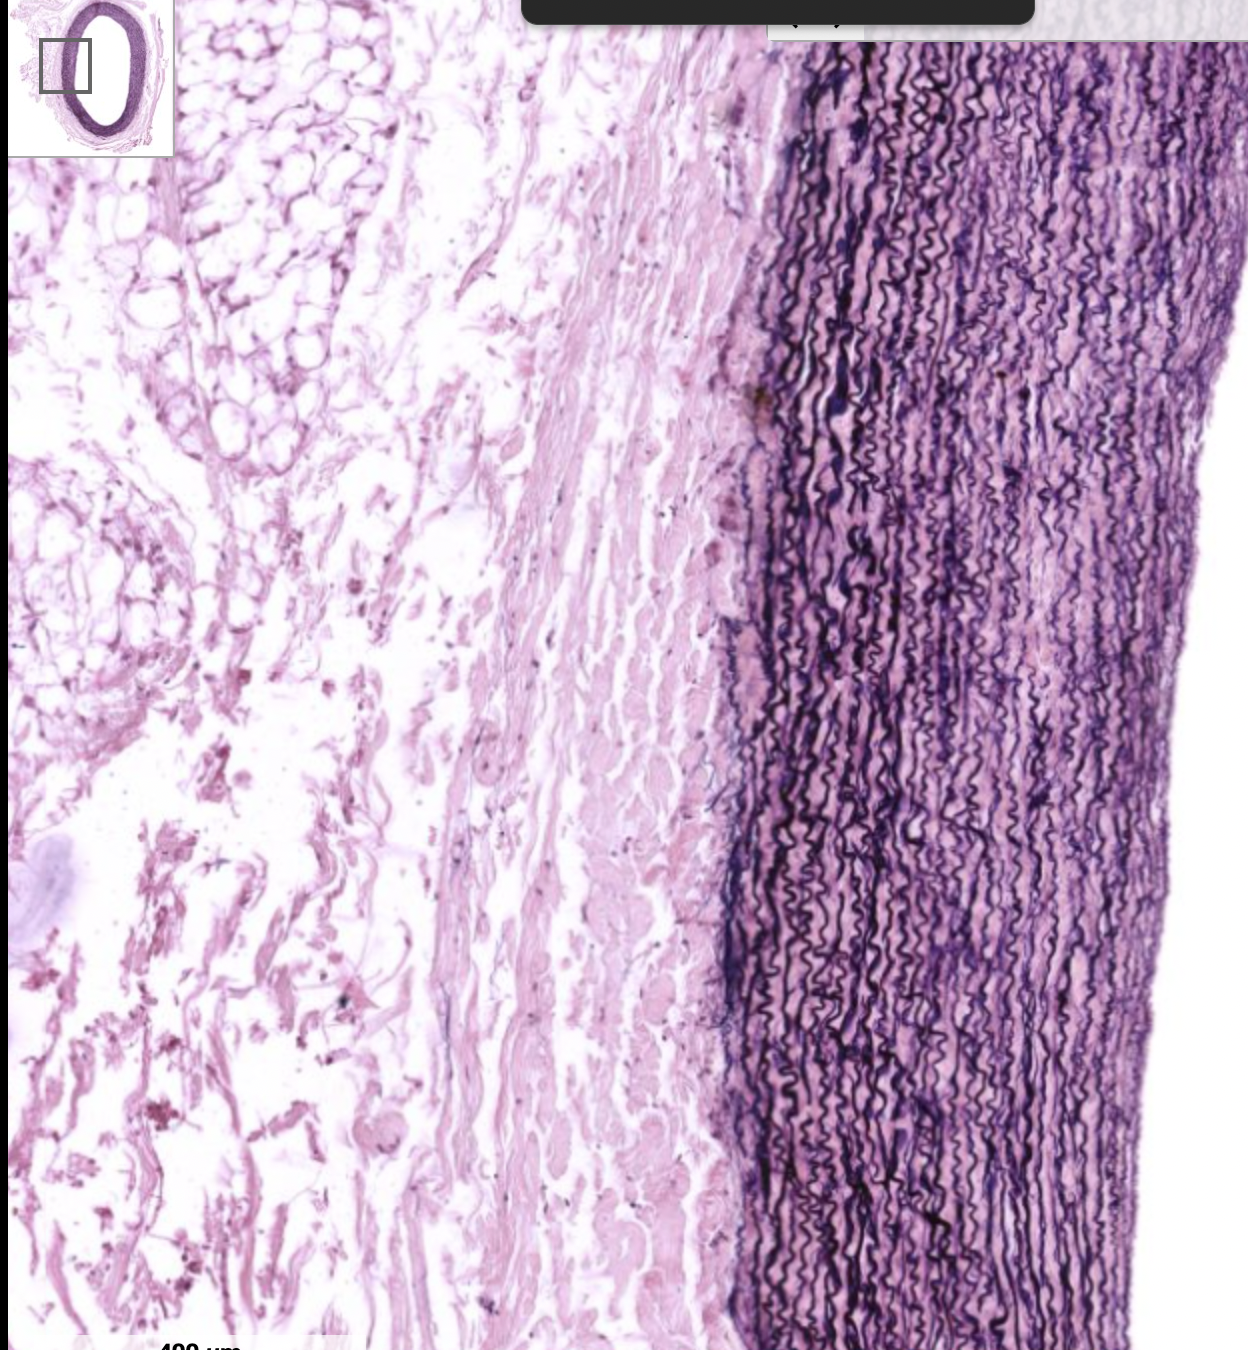

mucsular artery

WAVY TUNICA INTIMA

Less elastic lamellae more smooth muscle cells

Muscular Arteries:

Thick walls, tunica media are concentrated in smooth muscle

Tunica intima has internal elastic membrane (elastic fibers), separating from tunica media

External elastic membrane separating tunica media from tunica adventitia, more diffused than internal elastic membrane

Muscular artery:

Well developed internal elastic lamellae, causing waviness of tunica intima

Muscular artery

Darker brown = internal elastic lamellae